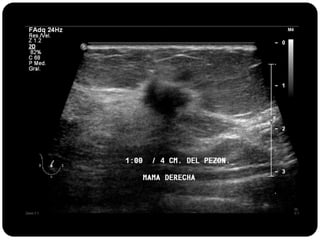

Paciente femenina de 66 años con historia clínica de 1er gesta antes de los 30 años y antecedentes de lactancia positiva, presenta una lesión palpable en la mama derecha. Los estudios radiológicos indican un diagnóstico de bi-rads 5, con biopsias revelando adenocarcinoma lobulillar infiltrante en la glándula mamaria derecha y adenocarcinoma ductal in situ en la izquierda. El caso fue evaluado por las doctoras Jacqueline Preciado Vargas y Beatriz E. González Ulloa.